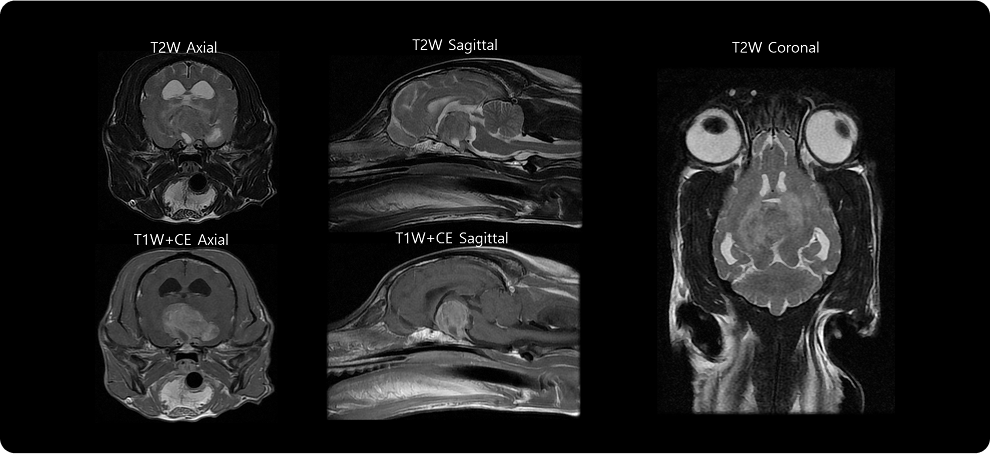

· 뇌 MRI 검사

신경계 증상이 동반된 경우, 시상하부의 종양성 변화 여부를 확인합니다.